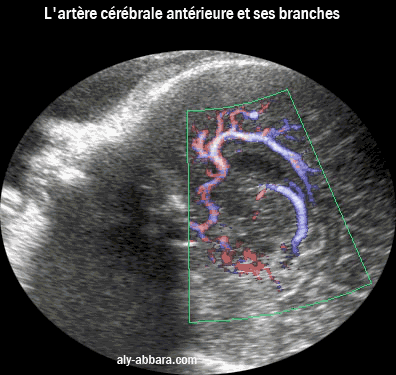

L'atère cérébrale antérieure et ses branches

L'artère cérébrale antérieure devenant l'artère péricalleuse et en arrière la veine cérébrale interne